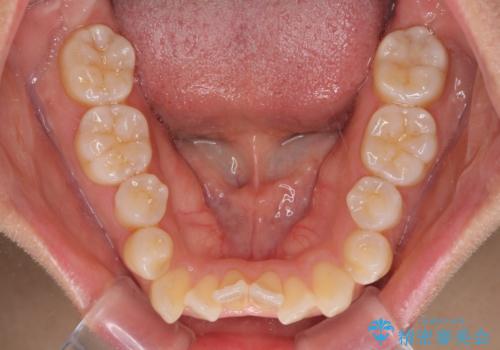

また、舌の突出癖の影響で上下前歯が接触していないオープンバイトとなっており、奥歯に負担のかかる咬み合わせとなっていました。

舌のトレーニングをしっかりと行ってくださり、前歯部のオープンバイトは大幅に改善されました。

もう少しでよりタイトに前歯が接触できそうでしたが、患者様がもう十分とのことで治療を終了しました。